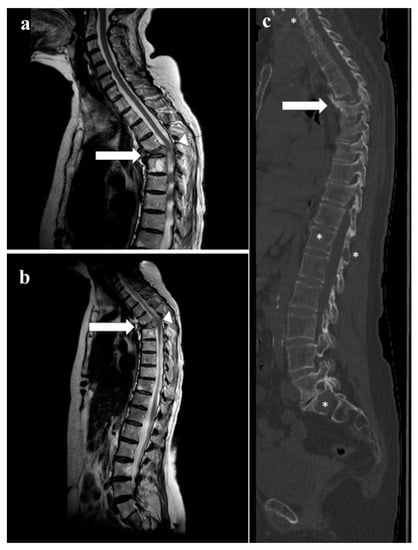

- Sureka, J.; Samuel, S.; Keshava, S.; Venkatesh, K.; Sundararaj, G. MRI in patients with tuberculous spondylitis presenting as vertebra plana: A retrospective analysis and review of literature. Clin. Radiol. 2013, 68, e36–e42. [Google Scholar] [CrossRef]

- Kaila, R.; Malhi, A.M.; Mahmood, B.; Saifuddin, A. The Incidence of Multiple Level Noncontiguous Vertebral Tuberculosis Detected Using Whole Spine MRI. J. Spinal Disord. Tech. 2007, 20, 78–81. [Google Scholar] [CrossRef]

- Haghighatkhah, H.; Jafroodi, Y.; Taheri, M.S.; Pourghorban, R.; Dehkordy, A.S. Multifocal Skeletal Tuberculosis Mimicking Langerhans Cell Histiocytosis in a Child: A Case Report with a Long-Term Follow-Up. Iran. Red. Crescent. Med. J. 2015, 17, e19942. [Google Scholar] [CrossRef] [PubMed]

- Kaeser, M.A.; Kettner, N.W.; Albastaki, U.; Kotb, H.A.; Eldesouky, I.M.; Pierre-Jerome, C. Tuberculous Spondylitis Presenting as Severe Chest Pain. Clin. Pr. 2012, 2, 42. [Google Scholar] [CrossRef]